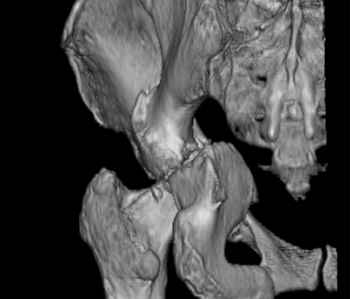

Уважаемые коллеги, возник вопрос по лечению нашей пациентки 60 лет. Около года назад множественная травма: в том числе Т-образный перелом вертлужной впадины. На сегодняшний день сращение отломков имеется на ограниченных участках, имеется дефект задней колонны вертлужной впадины. Движения неплохие, ходит с костылями, приступая на ногу. По мнению эдопротезистов при установке антипротрузионного кольца или октопуса не хватит костного материала и необходимо перед протезированием выполнить реконструкцию впадины, иначе чашка протеза неминуемо выпадет.Просьбы поделиться положительным и отрицательным опытом протезирования в подобных случаях.Возможно ли обойтись без реконструкции?Или лучше с ней?С уважением РАВ.